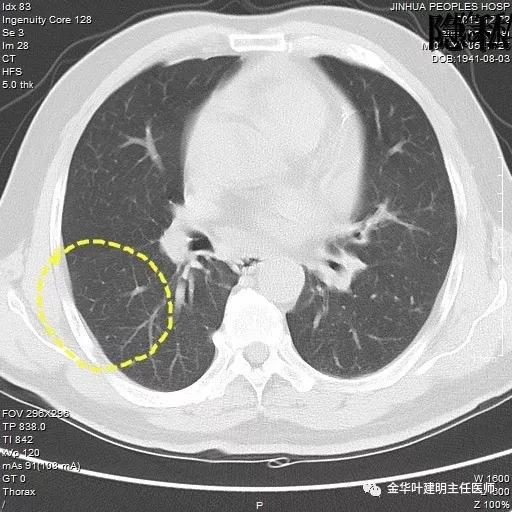

金华的周某,今年已经78岁了,上个月底单位退休人员体检,查出他的右肺有一结节,结果出来后,这个月通知他到胸外科复诊。因为是我的亲戚,便直接找到了我,我从电脑里调出他的CT片,如下所示:

可见其右下叶有一空腔性病灶,壁薄,病灶下方见到实性密度的成份。我们看过目前的片子后,马上想到的是此病灶以前有没有,对比是非常重要的。调出之前片子:

以上是2015年12月的片子,此处没有异常。